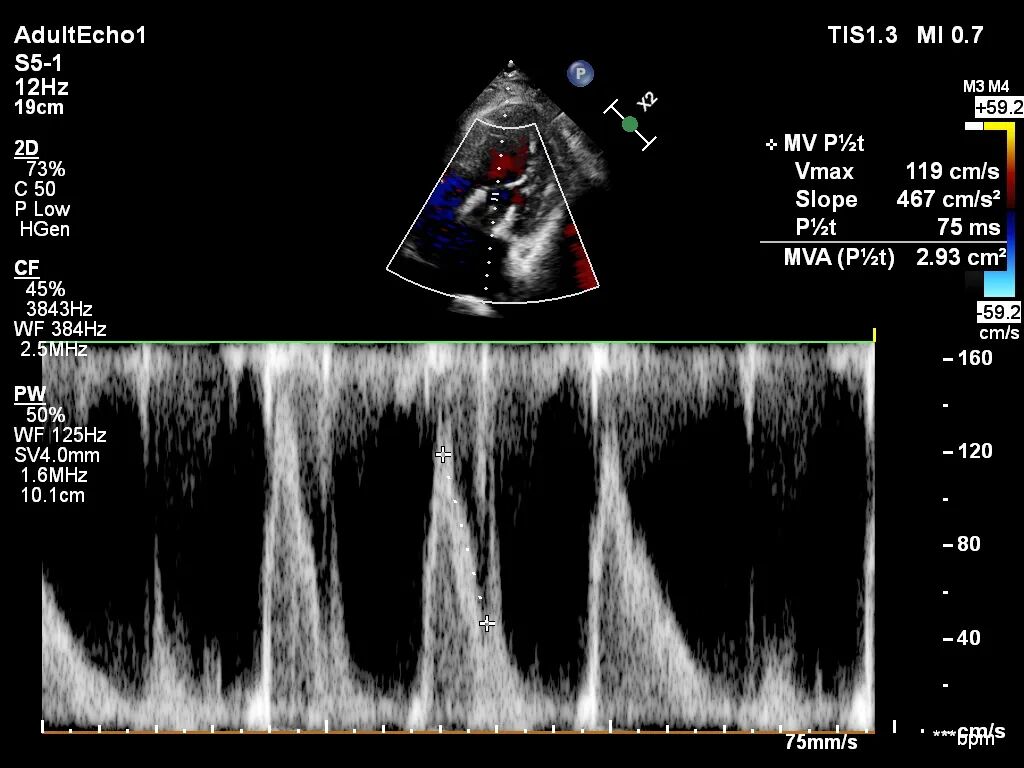

术后出院前检查结果

术后第2天患者出监护室,术后第4天拔管,术后第5天顺利出院。出院前心超显示:经导管二尖瓣人工瓣膜植入术后,人工瓣膜支架固定,形态未见异常,瓣叶开放不受限,瓣口由多普勒估测其开放峰值流速为1.15m/s,峰值压差5mmHg,平均跨瓣压差为2mmHg,由连续多普勒据PHT估测面积约2.93cm²,瓣叶关闭形态未见异常,彩色多普勒未测及二尖瓣反流及瓣周漏;左心室流出道通畅,流出道峰值流速0.93m/s。

出院时人工瓣膜开口面积

出院时人工瓣膜跨瓣压差